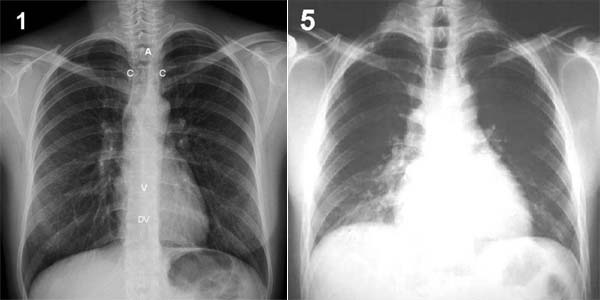

Placa 5 y placa 1